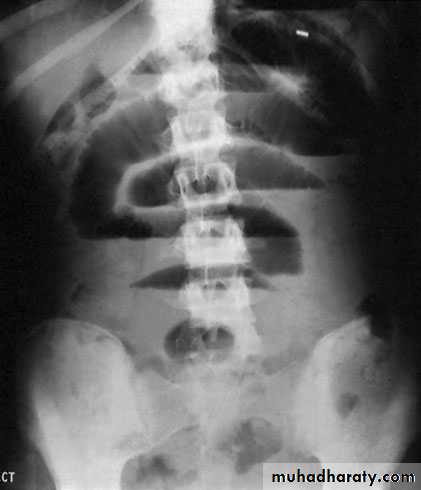

Clinical features of volvulus Sigmoid volvulusThe symptoms are of large bowel obstruction, which may initiallybe intermittent followed by the passage of large quantities offlatus and faeces.Abdominal distension is an early and progressive sign, which maybe associated with hiccough and retching; vomiting occurs late.Constipation is absolute.IMAGINGErect abdominal films are no longer routinely obtained and theradiological diagnosis is based on a supine abdominal film. An erect film may subsequently be requested when furtherdoubt exists.When distended with gas, the jejunum, ileum, caecum andremaining colon have a characteristic appearance in adults andolder children that allows them to be distinguished radiologically.

In intestinal obstruction, fluid levels appear later than gas shadowsas it takes time for gas and fluid to separate .These are most prominent on an erect film. In adults, two inconstant fluid levels – one at the duodenal cap and the other in the terminal ileum – may be regarded as normal.In infants (less than 1 year old), a few fluid levels in the small bowel may be physiological.

Imaging in volvulusIn caecal volvulus, radiography may reveal a gas-filled ileum andoccasionally a distended caecum. A barium enema may be usedto confirm the diagnosis, with an absence of barium in thecaecum and a bird beak deformity.In sigmoid volvulus, a plain radiograph shows massive colonicdistension. The classic appearance is of a dilated loop of bowel.